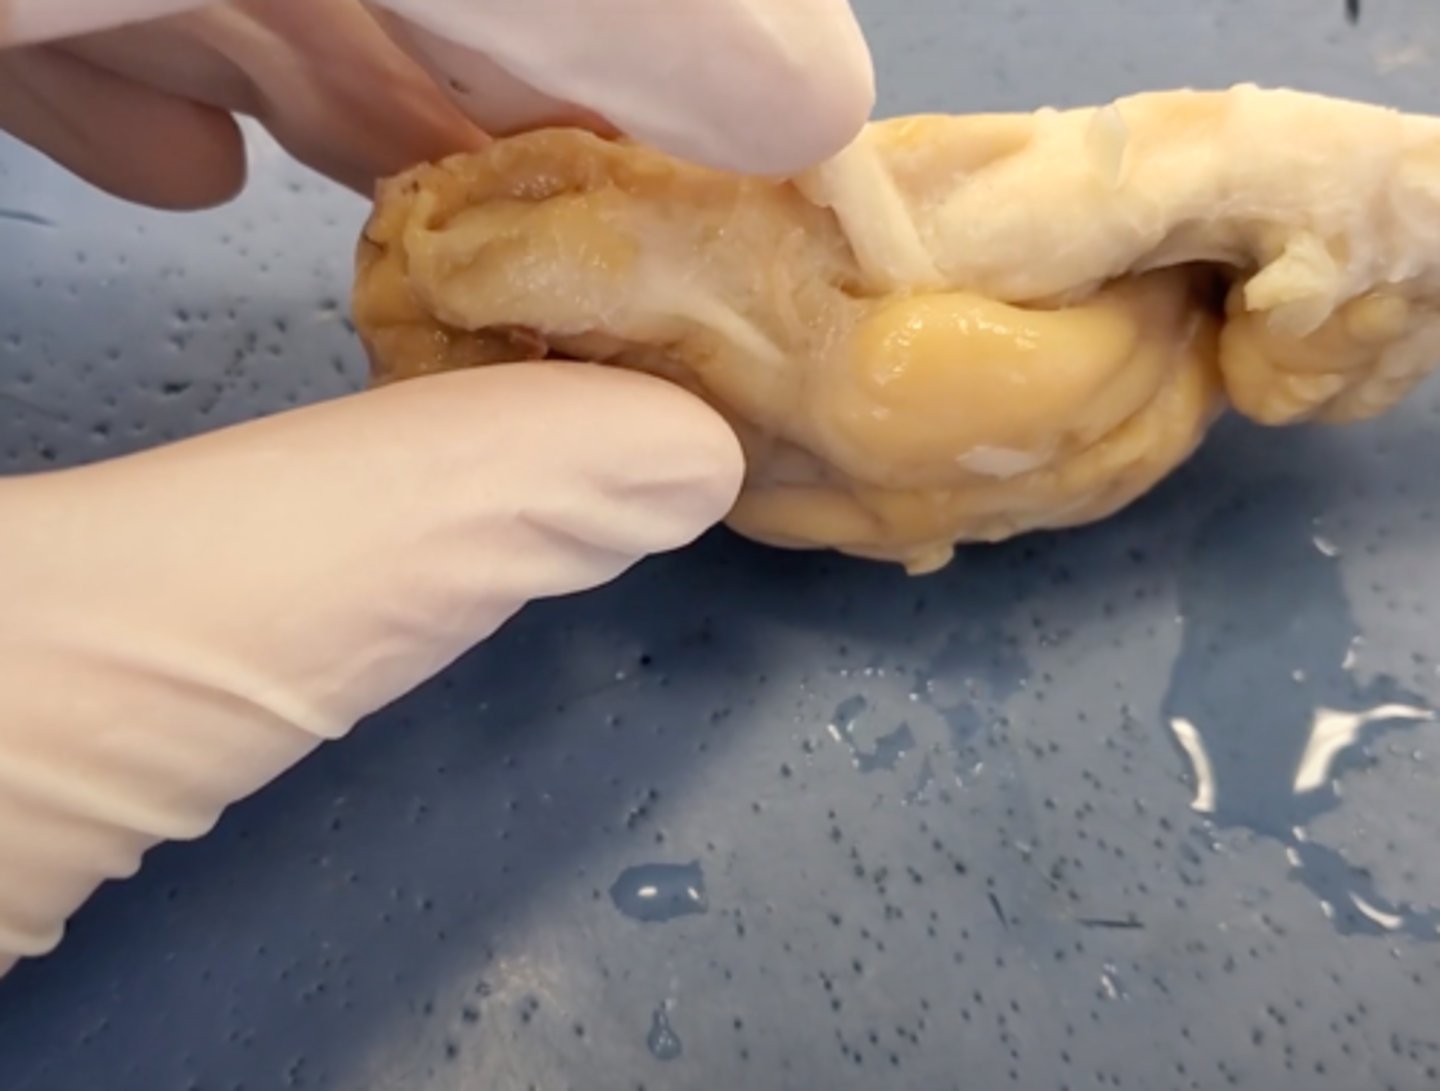

Central Nervous System (CNS)

brain and spinal cord, receives information from sensory receptors, coordinates and integrates the information, and initiates and transmits a response

peripheral nervous system (PNS)

nerves and ganglia, afferent (sensory) nerves channel impulses from sensory receptors to the CNS, and efferent (motor) nerves, which transmit impulses from the CNS to effector organs such as neurons, muscles, and glands.

cerebrum

Area of the brain responsible for all voluntary activities of the body

cerebellum

A large structure of the hindbrain that controls fine motor skills.

olfactory bulb

a brain structure located above the nasal cavity beneath the frontal lobes

medula oblongata

part of the brain that controls breathing, heartbeat, and the size of blood vessels

optic chiasma

the crossing of the optic nerves from the two eyes at the base of the brain

optic nerve

the nerve that carries neural impulses from the eye to the brain

corpus callosum

the large band of neural fibers connecting the two brain hemispheres and carrying messages between them